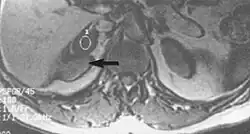

Metal artifacts

Metal artifacts occur at interfaces of tissues with different magnetic susceptibilities, which cause local magnetic fields to distort the external magnetic field. This distortion changes the precession frequency in the tissue leading to spatial mismapping of information. The degree of distortion depends on the type of metal (stainless steel having a greater distorting effect than titanium alloy), the type of interface (most striking effect at soft tissue-metal interfaces), pulse sequence and imaging parameters. Metal artifacts are caused by external ferromagnetics such as cobalt containing make-up, internal ferromagnetics such as surgical clips, spinal hardware and other orthopaedic devices, and in some cases, metallic objects swallowed by people with pica.[3] Manifestation of these artifacts is variable, including total signal loss, peripheral high signal and image distortion (Figs 3 and 4).[1] Reduction of these artifacts can be attempted by orientating the long axis of an implant or device parallel to the long axis of the external magnetic field, possible with mobile extremity imaging and an open magnet. Further methods used are choosing the appropriate frequency encoding direction, since metal artifacts are most pronounced in this direction, using smaller voxel sizes, fast imaging sequences, increased readout bandwidth and avoiding gradient-echo imaging when metal is present. A technique called MARS (metal artifact reduction sequence) applies an additional gradient, along the slice select gradient at the time the frequency encoding gradient is applied.